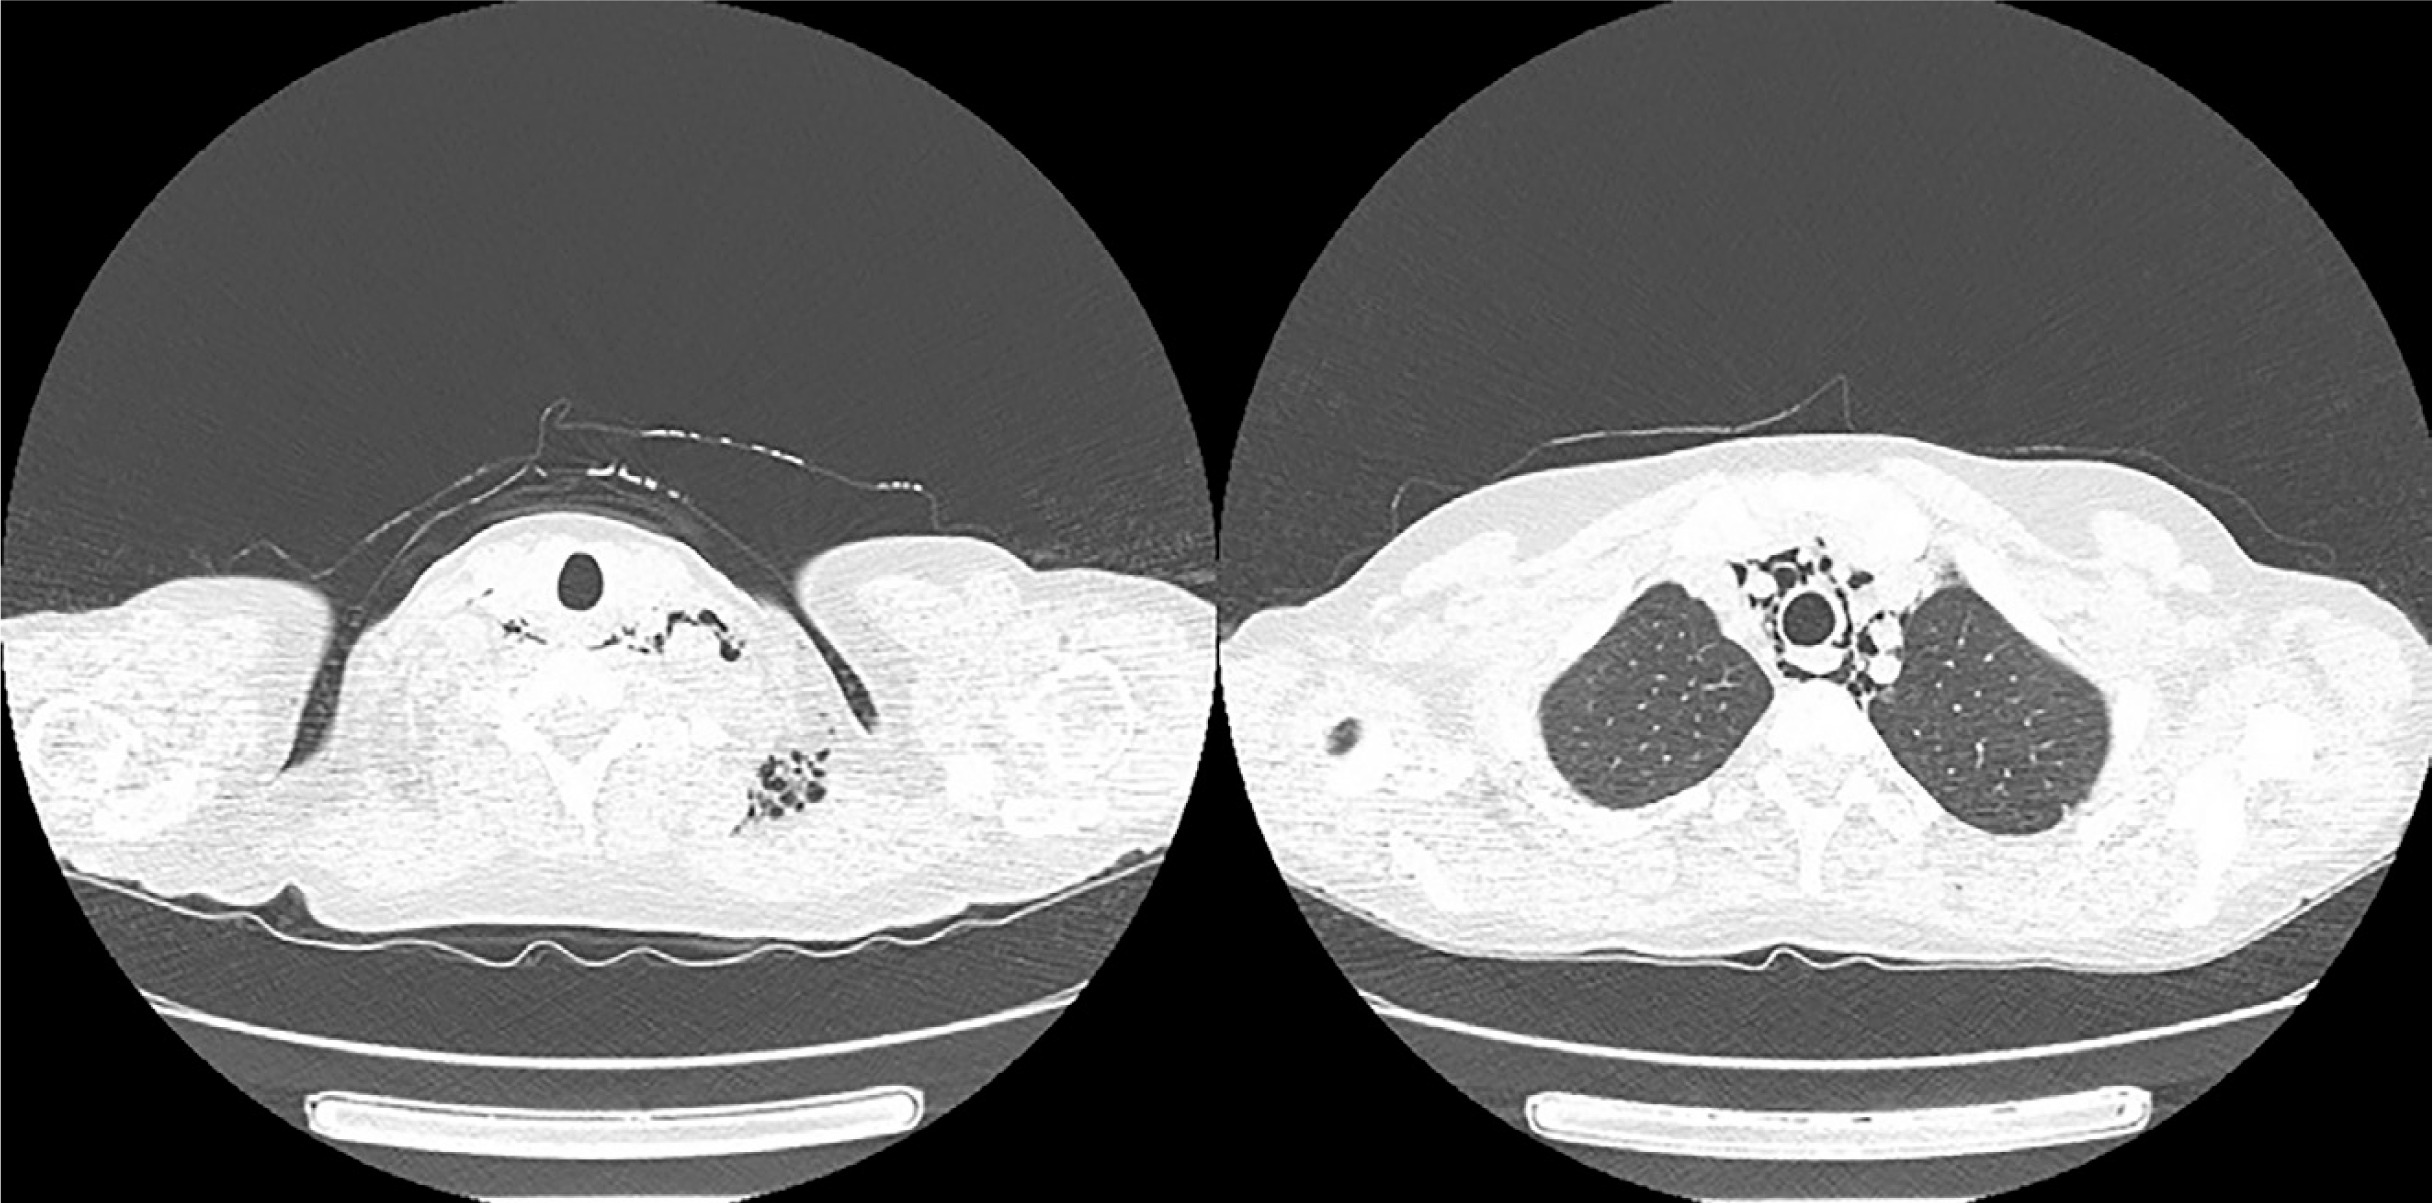

A 48-year-old female healthcare worker presented to the Emergency Department with dyspnoea and fever up to 39°C. The symptoms were accompanied by polyarthralgia, muscle weakness, general malaise and morning productive cough. Anamnesis revealed a history of sinus tachycardia, gastroesophageal reflux disease, increased levels of anti-thyroid peroxide and antithyroglobulin antibodies without clinically active thyroid disorder. Lung CT scan revealed diffuse infiltrates in the subpleural space in the bases of both lungs, thickening of interlobular septa and ground glass opacities, indicative for interstitial lung disease (ILD) in the phenotype of organizing pneumonia (OP). Swab test for COVID-19, flu and respiratory syncytial virus were negative.

Upon admission to the pneumonology department, the patient presented with heliotropic erythema accompanied by desquamating forehead lesions, Gottron’s papules above the small joints of the hands, nailfold erythema, telangiectasia, and swelling and tenderness of carpal and intercarpal joints. On auscultation, crackles in the bases of both lungs were detected. Laboratory investigations revealed elevated levels of ALT, AST and CK. Inflammatory markers such as CRP and ESR were subtly elevated, anti-cyclic citrullinated peptide antibodies likewise. Rheumatoid factor (RF) level was within the normal range. Antinuclear antibodies were positive, at a titre of 1 : 640, with 1 : 320 speckled type and 1 : 160 cytoplasmatic type. Myositis-specific antibodies immunoblot revealed strong positivity of anti-MDA5, while in ANA 3 profile, anti-Ro-52 and anti-DFS-70 antibodies were detected. There were no obstructive or restrictive abnormalities in spirometry. Plethysmography showed correct total lung capacity, with moderate diffusion disturbance in diffusion lung capacity for carbon dioxide (DLCO – 68%). The patient achieved 410 metres in the 6-Minute Walk Test without desaturation. A diagnosis of anti-MDA5-related DM with ILD-OP was proposed, based on the opinion of a multidisciplinary team (pneumonologists, rheumatologists, radiologists), and the patient was referred to the Rheumatology Department.